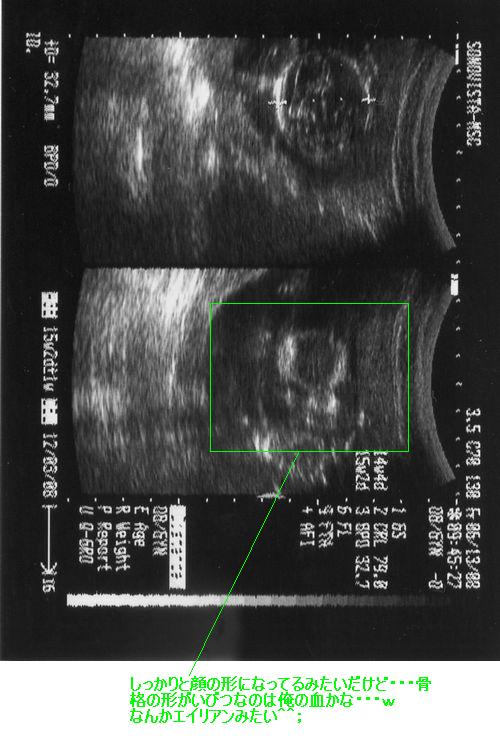

そしてもう一つのエコー写真ですが、緑の四角で囲ったところにエイリアンともターミネータとも見てとれる形がありますが、まぎれもなく正面から見た顔なんです。

この写真では分かりづらいですが、色々と角度を変えて見てみると頭蓋骨の形が少しいびつで蒼盾の頭の形とそっくりらしいんですよw

いらんところばっかり俺に似そうで;;